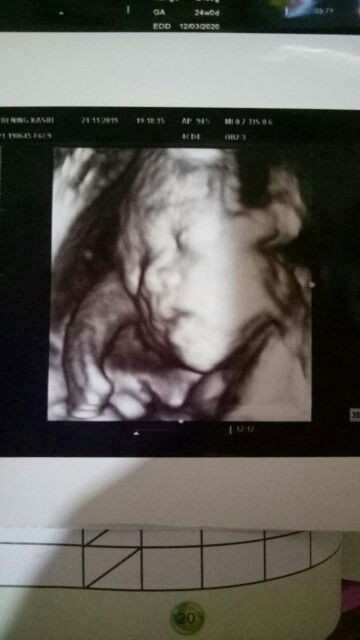

Kira² ini usg brp dimensi yaa soalnya ga diksih tau dokternya ??